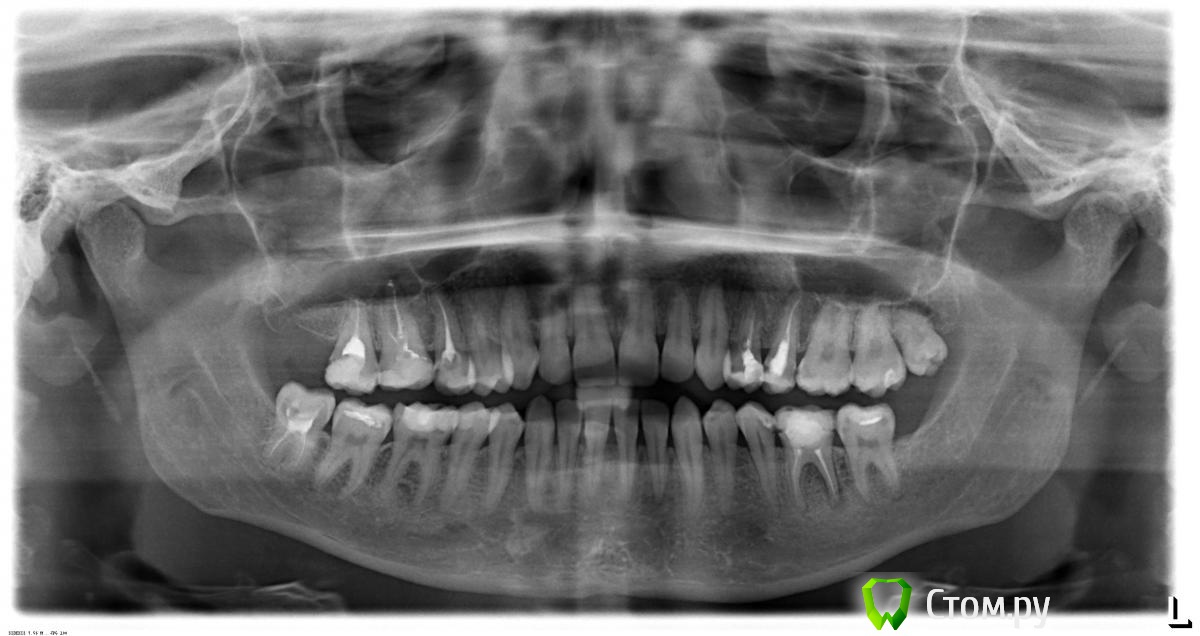

Евгения23 Опубликовано 17 сентября, 2014 Поделиться Опубликовано 17 сентября, 2014 Добрый день, нужна помощь специалистов. 3 дня назад начал ныть правая верхняя 7ка, на горячее-холодное реакциии нет, сильная боль возникает при накусывание. В стоматологии начали говорить о воспалении в надкостнице и об удалении зуба. Прошу прокомментировать. Заранее спасибо. Ссылка на комментарий

Евгения23 Опубликовано 17 сентября, 2014 Автор Поделиться Опубликовано 17 сентября, 2014 поясню, зуб депульпирован много лет назад, сейчас появилась боль при накусывании, сделала вчера только снимок и получила консультацию стоматолога, пока взяла время подумать и проконсультироваться с другими специалистами. Ссылка на комментарий

anvladd Опубликовано 17 сентября, 2014 Поделиться Опубликовано 17 сентября, 2014 Посмотреть бы прицельный снимок,по этому снимку мне показалась перфорация в области медиального щечного корня(со стороны 5го зуба). Ссылка на комментарий